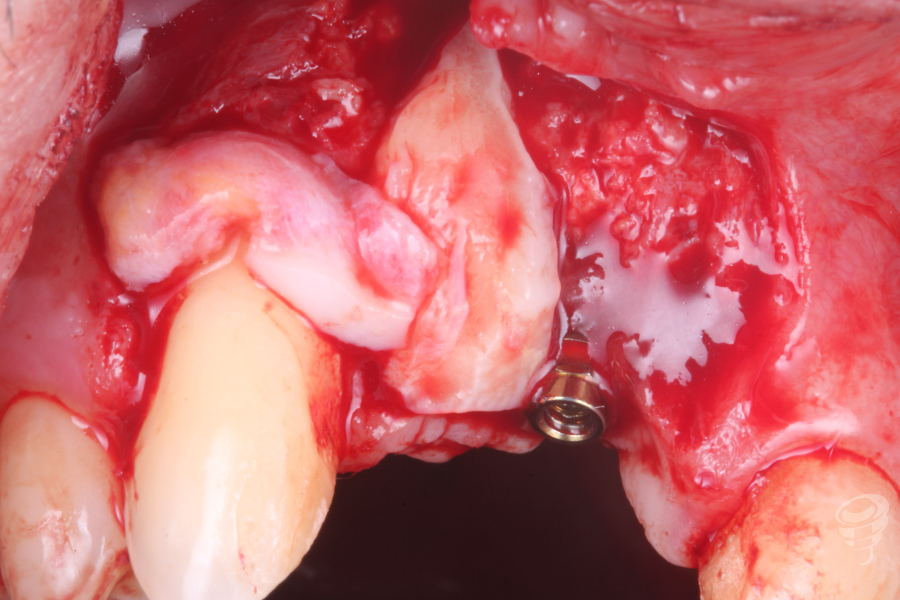

Seis meses después se levanta un colgajo a espesor total y retiramos el tornillo de Tent Pole, pudiendo observar el relleno total de la zona injertada.

Imagen 11

Imagen 12

Además en esta cirugía realizamos un injerto de tejido conectivo para ganar más volumen en sentido vestibular.

Imagen 13

Imagen 14